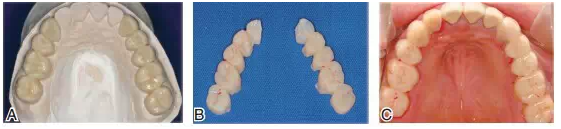

圖13將上頜模型、蠟板、石膏平臺一起上平均值牙合架,取下蠟板后,在蠟板和石膏平臺之間留下的空隙內(nèi),用白色嵌體蠟雕刻后牙的牙冠形態(tài),形成恢復(fù)上頜正常牙合平面的診斷蠟型

圖14根據(jù)診斷蠟型制作暫時冠戴入上頜。A.上頜后牙診斷蠟型;B.根據(jù)診斷蠟型翻制的暫時冠;C.暫時冠戴入口內(nèi)